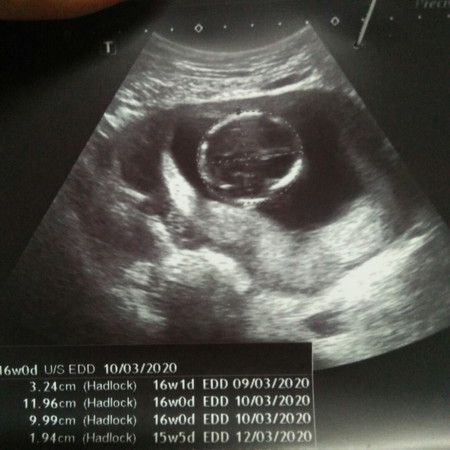

ตั้งครรภ์ 16สัปดาห์

คุณหมออุลตร้าซาวด์แต่ยังไม่บอกเพศจร้าาตอนนี้ลุ้นอยู่ค่ะว่าเพศอะไร คุณแม่พอดูออกมั้ยค่ะว่าเพศไหน

อันนี้ส่วนหัวน้องค่ะคุณแม่... 16 weeks ถ้าเป็นผู้ชาย และน้องไม่หนีบขา คุณหมอสามารถบอกได้เลยค่ะว่าเป็นผู้ชาย แต่ถ้าคุณหมอยังไม่บอกอาจมีลุ้นว่าเป็นผู้หญิงค่ะ 💕

อันนี้รูปหัวน้องค่ะแม่ไม่ใช่รูปที่ดูเพศน้อง ถ้าแม่อยากรู้เพศน้องลองไปซาวคลีนิคดูค่ะ

รูปนี้ส่วนศรีษะน้องค่ะ แม่ต้องเอารูปหว่างขาน้องมาดูค่ะถึงจะดูออก

อันนี้หมอวัดหัวน้องค่ะ แม่ลองเอาใบซาวอันอื่นมาลงแทนค่ะ

แม่ต้องดูภาพที่ซาวด์เห็นช่วงล่างน้องค่ะ อันนี้ส่วนหัว

ขนาดกระโหลกศีรษะน้องค่ะ ดูเพศไม่ได้จ้า